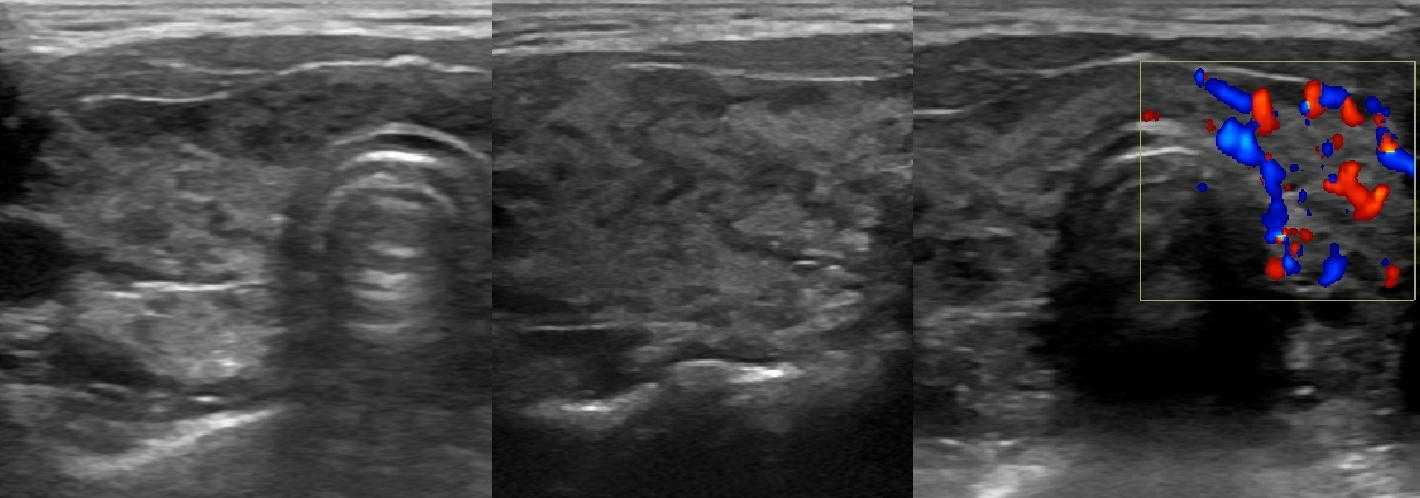

Рисунок. Девочка 10-ти лет с эутиреозом и антитиреоидными антителами. На УЗИ щитовидная железа увеличена в 1,5 раза — 13 см3 (норма до 8,3 см3). На фоне неизмененной паренхимы определяются гипоэхогенные «змеи» (лимфоидная инфильтрация по ходу сосудов). Кровоток заметно усилен. Заключение: АИТ, гипертрофическая форма. Аналогично может начинаться диффузный токсический зоб.